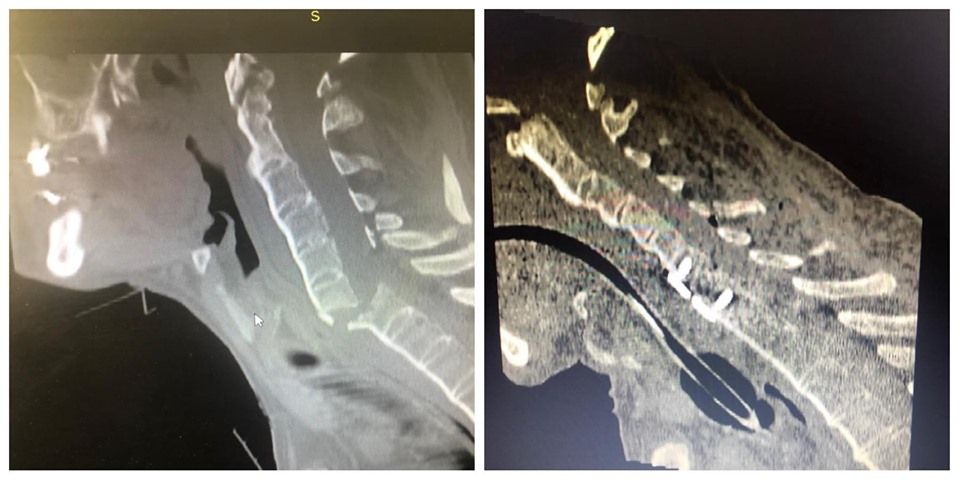

31 mai 2019, 17:54ActualitateIntervenție chirurgicală complexă, care a durat 5 ore, efectuată de medicii neurochirurgi de la Spitalul Județean de Urgență Bistrița